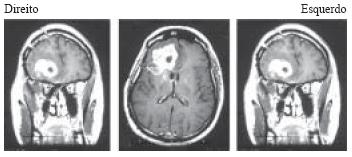

As imagens de RNM, com seqüências ponderadas em T1, feitas com contraste gadolíneo, mostram a presença de um processo expansivo na região frontal direita.

Enunciado 799576-1

O achado anátomo- patológico mais relacionado à piora do prognóstico do tumor apresentado é